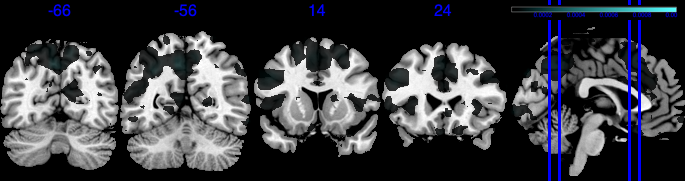

| Posterior inclusion probability (color range ) |

![]() |

| Positive posterior mean of the spatial mediation effects (color range ) |

| Negative posterior mean of the spatial mediation effects (color range ) |

We performed 100,000 iterations for the outcome model (1), discarding the first 50% as burn-in and thinning to retain 1,000 posterior samples. For the mediator model (2), we ran 40,000 iterations with a 30,000 burn-in, thinning every 10 iterations to obtain 1,000 posterior samples. Table 3 gives a summary of both the overall NIE and NDE and the top seven regions identified with the largest number of active voxels. The definition of NIE in each region is , where is the collection of all voxels in region . The rule for selecting the active voxels is based on cutting the posterior inclusion probability (PIP) at 50%, and the three regions with active voxels are reported in Table 3. Due to the very small effect sizes and low signal-to-noise ratio, we also include regions with voxels’ PIP greater than 10%. The posterior of NDE has a mean of 0.27 with the 95% credible interval . The posterior of NIE has a mean of 0.0885 with the 95% credible interval . The total effect of parental education level on general cognitive ability score is 0.36, with 95% credible interval (0.29,0.45). This suggests that parents with college degrees have a positive impact on children’s cognitive abilities, and about 25% of the effect is mediated through brain cognitive development. Figure 5 shows the estimated activation regions and the NIE in coronal view slides. Among the top identified activation regions, the most interesting is the left precuneus, which plays a key role in episodic memory, visuospatial processing, and self-consciousness (lou2004parietal; wallentin2006parallel). This region has been consistently implicated in cognitive processes related to memory retrieval and spatial awareness, which are crucial components of children’s cognitive development. In addition, other identified regions, such as the left inferior parietal region and the left postcentral gyrus, are associated with the interpretation of sensory information (radua2010neural; diguiseppi2023neuroanatomy). These regions are involved in integrating and processing sensory inputs, which are essential for tasks that require coordination between perception and cognition, such as working memory and executive function. These findings align with existing literature on the neural correlates of cognitive function, particularly in children. By identifying regions that have been consistently associated with cognitive processes, our results not only demonstrate the scientific validity of the BIMA approach but also provide meaningful insights into the brain areas that underlie cognitive abilities as captured by the ABCD study.